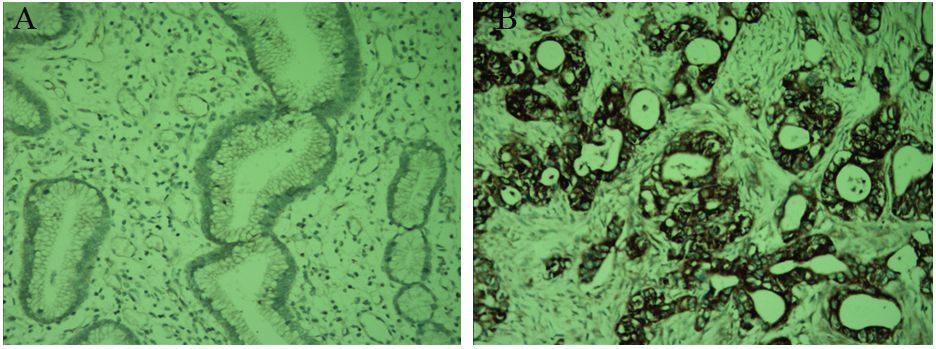

Id-1在结直肠癌组织中的阳性表达72.00%(36/50)明显高于癌旁组织24.00%(12/50),两者比较差异有统计学意义(χ2=23.431,P=0.000); MMP-9在结直肠癌组织中的阳性表达为78%(39/50),明显高于癌旁组织28.00%(14/50),两者比较差异有统计学意义(χ2=18.944,P=0.000);结直肠癌组织中LMVD表达(15.18±2.16)明显高于癌旁组织(5.24±1.09),两者比较差异有统计学意义(t=25.051,P=0.000),见图 1,表 1。

![]() 图 1 免疫组织化学法检测Id-1、MMP-9在结直肠癌癌旁与癌组织中的表达和LMVDFigure 1 Expression of Id-1,MMP-9 and LMVD in colorectal normal adjacent and colorectal tissues detected by IHC methodA: positive expression of Id-1 in colorectal normal adjacent tissues; B: positive expression of Id-1 in colorectal carcinoma tissues; C : positive expression of MMP-9 in colorectal normal adjacent tissues; D: positive expression of MMP-9 in colorectal carcinoma tissues; E: positive expression of LMVD markd by D-240 in colorectal carcinoma tissues (IHC ×200)表 1 Id-1、MMP-9在结直肠癌癌旁与癌组织中的表达和LMVDTable 1 The expressions of Id-1,MMP-9 and LMVD in colorectal normal adjacent tissues and colorectal carcinoma tissues

图 1 免疫组织化学法检测Id-1、MMP-9在结直肠癌癌旁与癌组织中的表达和LMVDFigure 1 Expression of Id-1,MMP-9 and LMVD in colorectal normal adjacent and colorectal tissues detected by IHC methodA: positive expression of Id-1 in colorectal normal adjacent tissues; B: positive expression of Id-1 in colorectal carcinoma tissues; C : positive expression of MMP-9 in colorectal normal adjacent tissues; D: positive expression of MMP-9 in colorectal carcinoma tissues; E: positive expression of LMVD markd by D-240 in colorectal carcinoma tissues (IHC ×200)表 1 Id-1、MMP-9在结直肠癌癌旁与癌组织中的表达和LMVDTable 1 The expressions of Id-1,MMP-9 and LMVD in colorectal normal adjacent tissues and colorectal carcinoma tissues